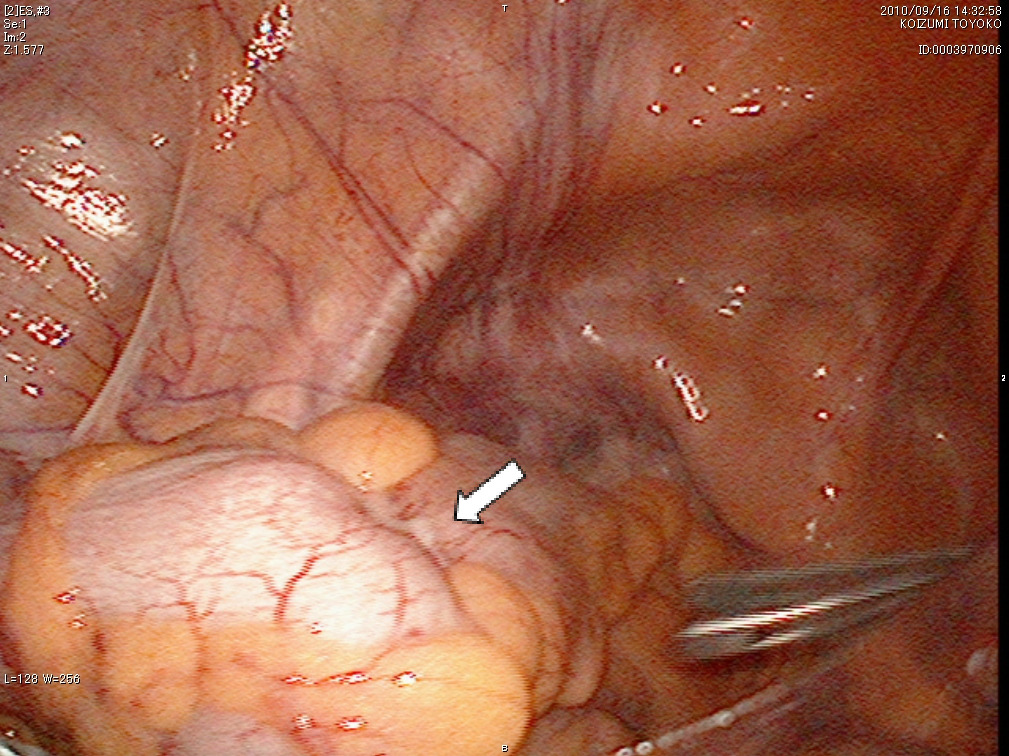

- 結腸がんの手術

結腸がんの手術では、がん病巣と周囲のリンパ節を同時に切除するために、がんの部位から10cmほど離れた腸管を切除し、断端をつなぎ合わせます。がんの存在部位により、回盲部切除術、右半結腸切除術、横行結腸切除術、左半結腸切除術、S状結腸切除術などの方法があります。がんを切除できない場合には、便の迂回路をつくるバイパス術やお腹に人工肛門(ストマ)をつくる手術を行うことがあります。 - 直腸がんの手術

腹腔鏡下S状結腸切除術の術野

a)病変部位(⇩)